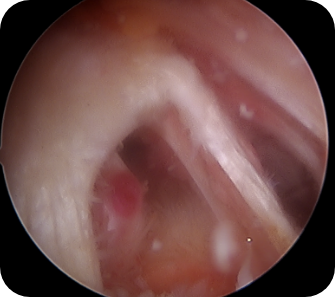

회전근개 질환, 오십견, 어깨 탈구 등 어깨 질환은 어깨의 통증과 고통을 야기합니다. 어깨 관절내시경 수술은 관절 질환이 의심되는 부위를 1cm 미만으로 최소절개한 뒤, 내시경 카메라와 수술 기구를 관절 내부에 삽입해 질환을 진단하고 치료하는 수술입니다. 화면을 통해 병변 부위를 직접 확인할 수 있어 손상 정도에 따라 파열된 힘줄을 봉합하거나 염증을 제거할 수 있습니다. CT나 MRI 등의 진단으로 잘 보이지 않던 곳까지 내시경을 삽입할 수 있어 적용 범위가 점점 넓어지고 있는 추세입니다.

- 오십견의 치료에 효과적입니다.

- 파열된 어깨관절을 복구시킬 수 있습니다.

- 관절 내 유리체를 제거할 수 있습니다.